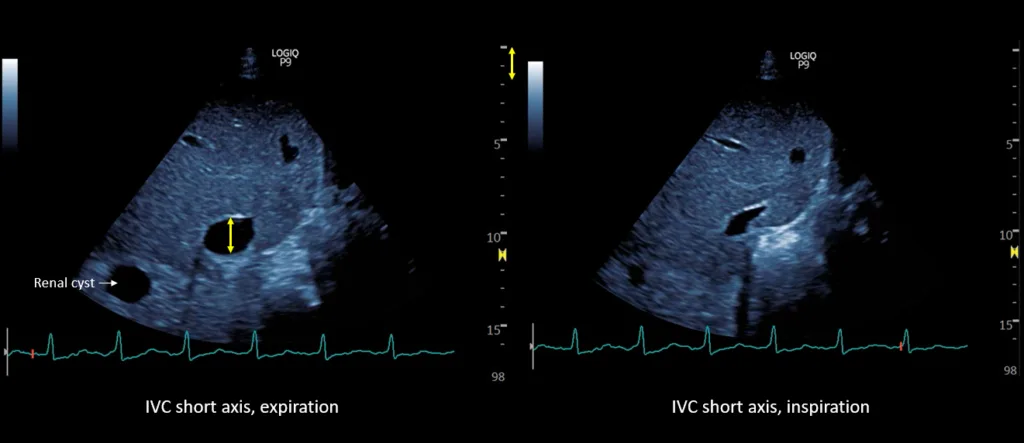

The IVC maximal diameter improved to approximately 2.1 cm, with >50% inspiratory collapse with an estimated right atrial pressure of 8 mmHg (Figure 5). Follow up POCUS after the third session demonstrated further improvement in IVC size (<2 cm), and collapsibility consistent with an estimated right atrial pressure of 3 mmHg (Figure 6). Remarkably, the shape of the IVC shifted from circular to oval during the decongestion of the patient, which is a clinically useful qualitative parameter. Hepatic vein Doppler demonstrated further improvement in S-wave amplitude to near-normal configuration, and the portal vein remained continuous (Figure 7). Intrarenal venous Doppler was not performed, as it is unreliable in ESKD.

Figure 5. Inferior vena cava ultrasound short axis demonstrating the maximal anteroposterior diameter (approximately 2.1 cm) and inspiratory collapse.

Figure 6. Inferior vena cava ultrasound short axis demonstrating the maximal anteroposterior diameter (approximately 1.9 cm) and inspiratory collapse.